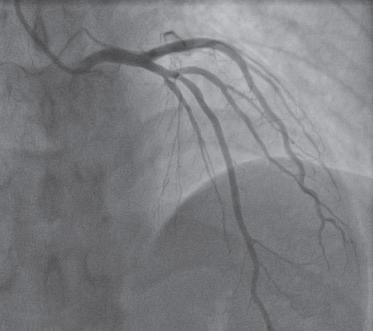

以桡骨茎突近端2cm可扪及桡动脉搏动处为进针点,常规消毒铺巾,用利多卡因逐层麻醉,显效后穿刺桡动脉,成功后常规置入6F桡动脉鞘,沿鞘管注入肝素钠注射液3000U、硝酸甘油200μg,在X线透视下,经鞘管送入直径0.035in(1in=2.54cm)、长260cm的超滑导丝,沿桡动脉、肱动脉、锁骨下动脉、主动脉弓到达升主动脉,再经导丝送入5F TIG导管至主动脉窦口,退出导丝,调整导管开口位置,分别在左、右冠状动脉开口与血管腔同轴后注入碘造影剂(图1-11、图1-1-2),血管显影后查看血管情况。造影完成后退出导管,桡动脉穿刺口予桡动脉止血器压迫止血,送患者安返病房。

图1-1-1 冠状动脉旋支造影